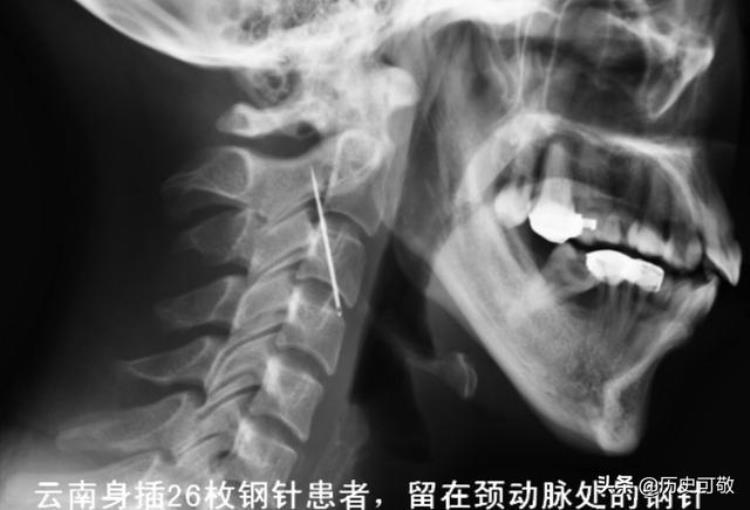

医生告诉罗翠芬“我要告诉你一个不好的消息,你颈部的针离大动脉非常的近,还有一根针在心脏附近,如果不及时治疗的话,随时都有生命的危险,你的尿之所以呈现鲜红色,是因为有一根针扎到你的膀胱和子宫上,因为后期感染,你的右肾已经萎缩,这个情况与你膀胱和子宫上的针有很大的关联”。

正因为手术难度极高,所以预计分为两期进行,第一期先取出头部和颈部的针,因此这里的针离血管太近,喉咙处的钢针马上就要扎到主动脉血管,因此尤为重要。

医生提供了一个重要的信息,那就是头部的那根钢针肯定是一岁之前扎进去的,当时罗翠芬处于婴儿期,头部比较脆弱,针才能够扎进去,随着年龄的增长,头部越来越硬,4厘米的钢针就难扎进去了。